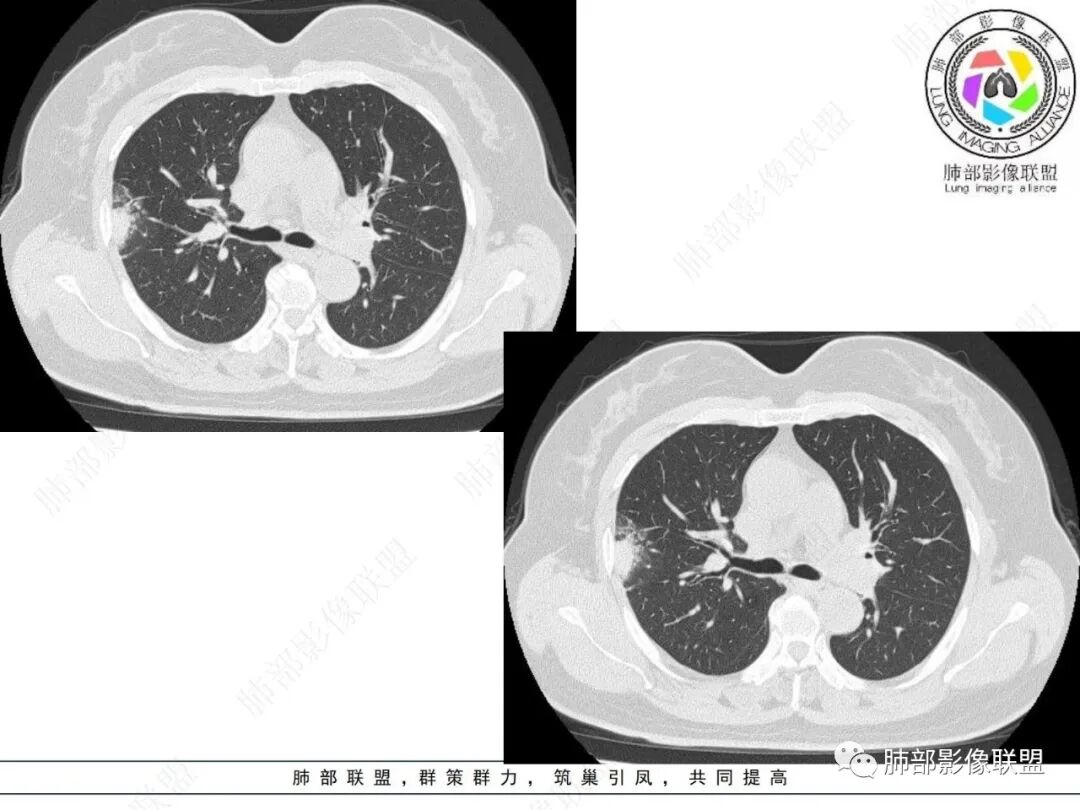

2.影像特点:

右肺上叶胸膜下混合磨玻璃团片影。

周围磨玻璃部分间杂条索状高密度区,密度欠均匀(可疑重力分布趋势),其磨玻璃影边界大多较清楚或可分辨,部分“L型”边缘,提示小叶间隔阻挡可能。血管穿行自如,可疑远端支气管进入。

实性部分较密实,不规则,隐约见棘突或刺状突起,未见钙化、空洞或液化区,实性边缘可见斑状略低密度间隙(借用王兆宇老师课件,称其呈“松软”的形态)。动脉期实性部分较明显不均匀强化,如果有完整增强图,还可以观察内部血管情况。

纵隔窗相对肺窗病灶相对小,仅部分实性影呈现。病灶张力不高,相邻胸膜增厚(糊墙),未见明显胸膜牵拉凹陷。

未见卫星病灶,远处未见磨玻璃结节影。

双肺门及纵隔未见明显增大淋巴结。心包及胸腔未见积液。